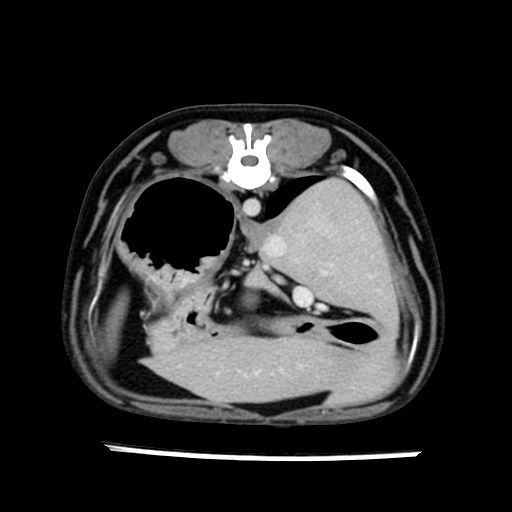

prescritto esame TAC

sequenza immagini limitata al fegato reni e surreni

le immagini ecografiche rispetto alla tac datano circa 7 mesi prima ,le surrenali sono normali nonostante il test acth sia risultato positivo .all’esame TAC dopo diversi mesi risultano aumentate armonicamente nel volume e si individua un forte sospetto di adenoma ipofisario .

sospetto adenoma ipofisario vs. meno probabilmente meningioma della base; intertiziopatia polmonare; lesione espansiva epatica, verosimilmente del lobo laterale sinistro, di sospetta natura neoplastica; lesioni spleniche di natura da definire; iperplasia/ipertrofia delle ghiandole surrenali, bilateralmente; vertebra di transizione del rachide toracico; tenosinovite cronica del muscolo bicipite brachiale di destra.

la tac dopo 7 mesi permette misure tridimensionali 5,2 x 9,2 x 4,5 cm (forma piu’ allungata )